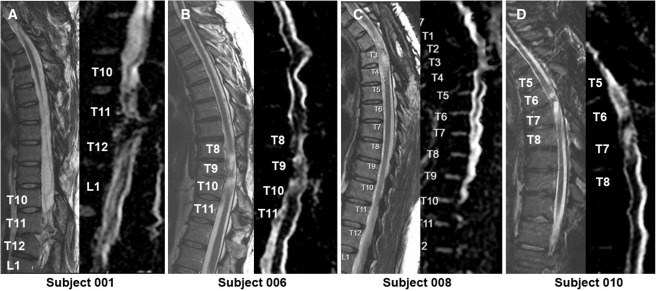

本次發布的I期臨床研究旨在評估神經干細胞移植治療慢性胸椎脊髓損傷的安全性和初步療效。研究選取了四名完全性ASIA-A級胸部SCI患者作為受試者,這些患者的損傷時間均超過一年,且在接受任何其他形式的有效治療后仍未見明顯好轉。

每位受試者接受了每個注射點含有2×105個神經干細胞,通過定制的立體定向設備,雙側注入損傷部位周圍的剩余組織及下方約一個節段的內側白質區,整個過程由術中熒光透視成像指導完成。

1.神經系統反應概覽:按ISNCSCI隨訪,2名受試者(001、010)在移植后出現了明顯的神經學改善:001在移植后2年曾上升兩個節段,5年回落至上升1個節段;010則在整個5年隨訪期間保持了穩定的神經功能提升。

4.影像學評估:術后MRI顯示所有患者存在不同程度的局灶性脊髓軟化,但未見新的并發影像學征象(如水腫、增強或積液);DTI提示脊髓束外觀穩定,未見廣泛重塑或纖維束改善。